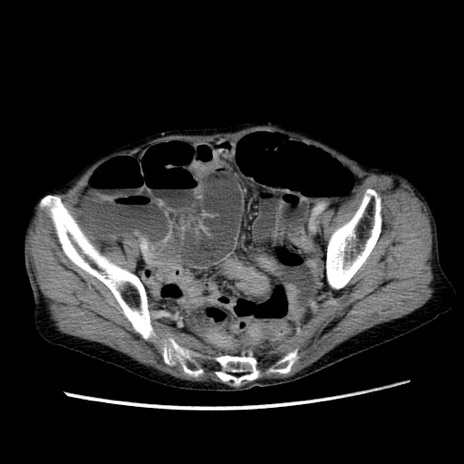

冠状断像